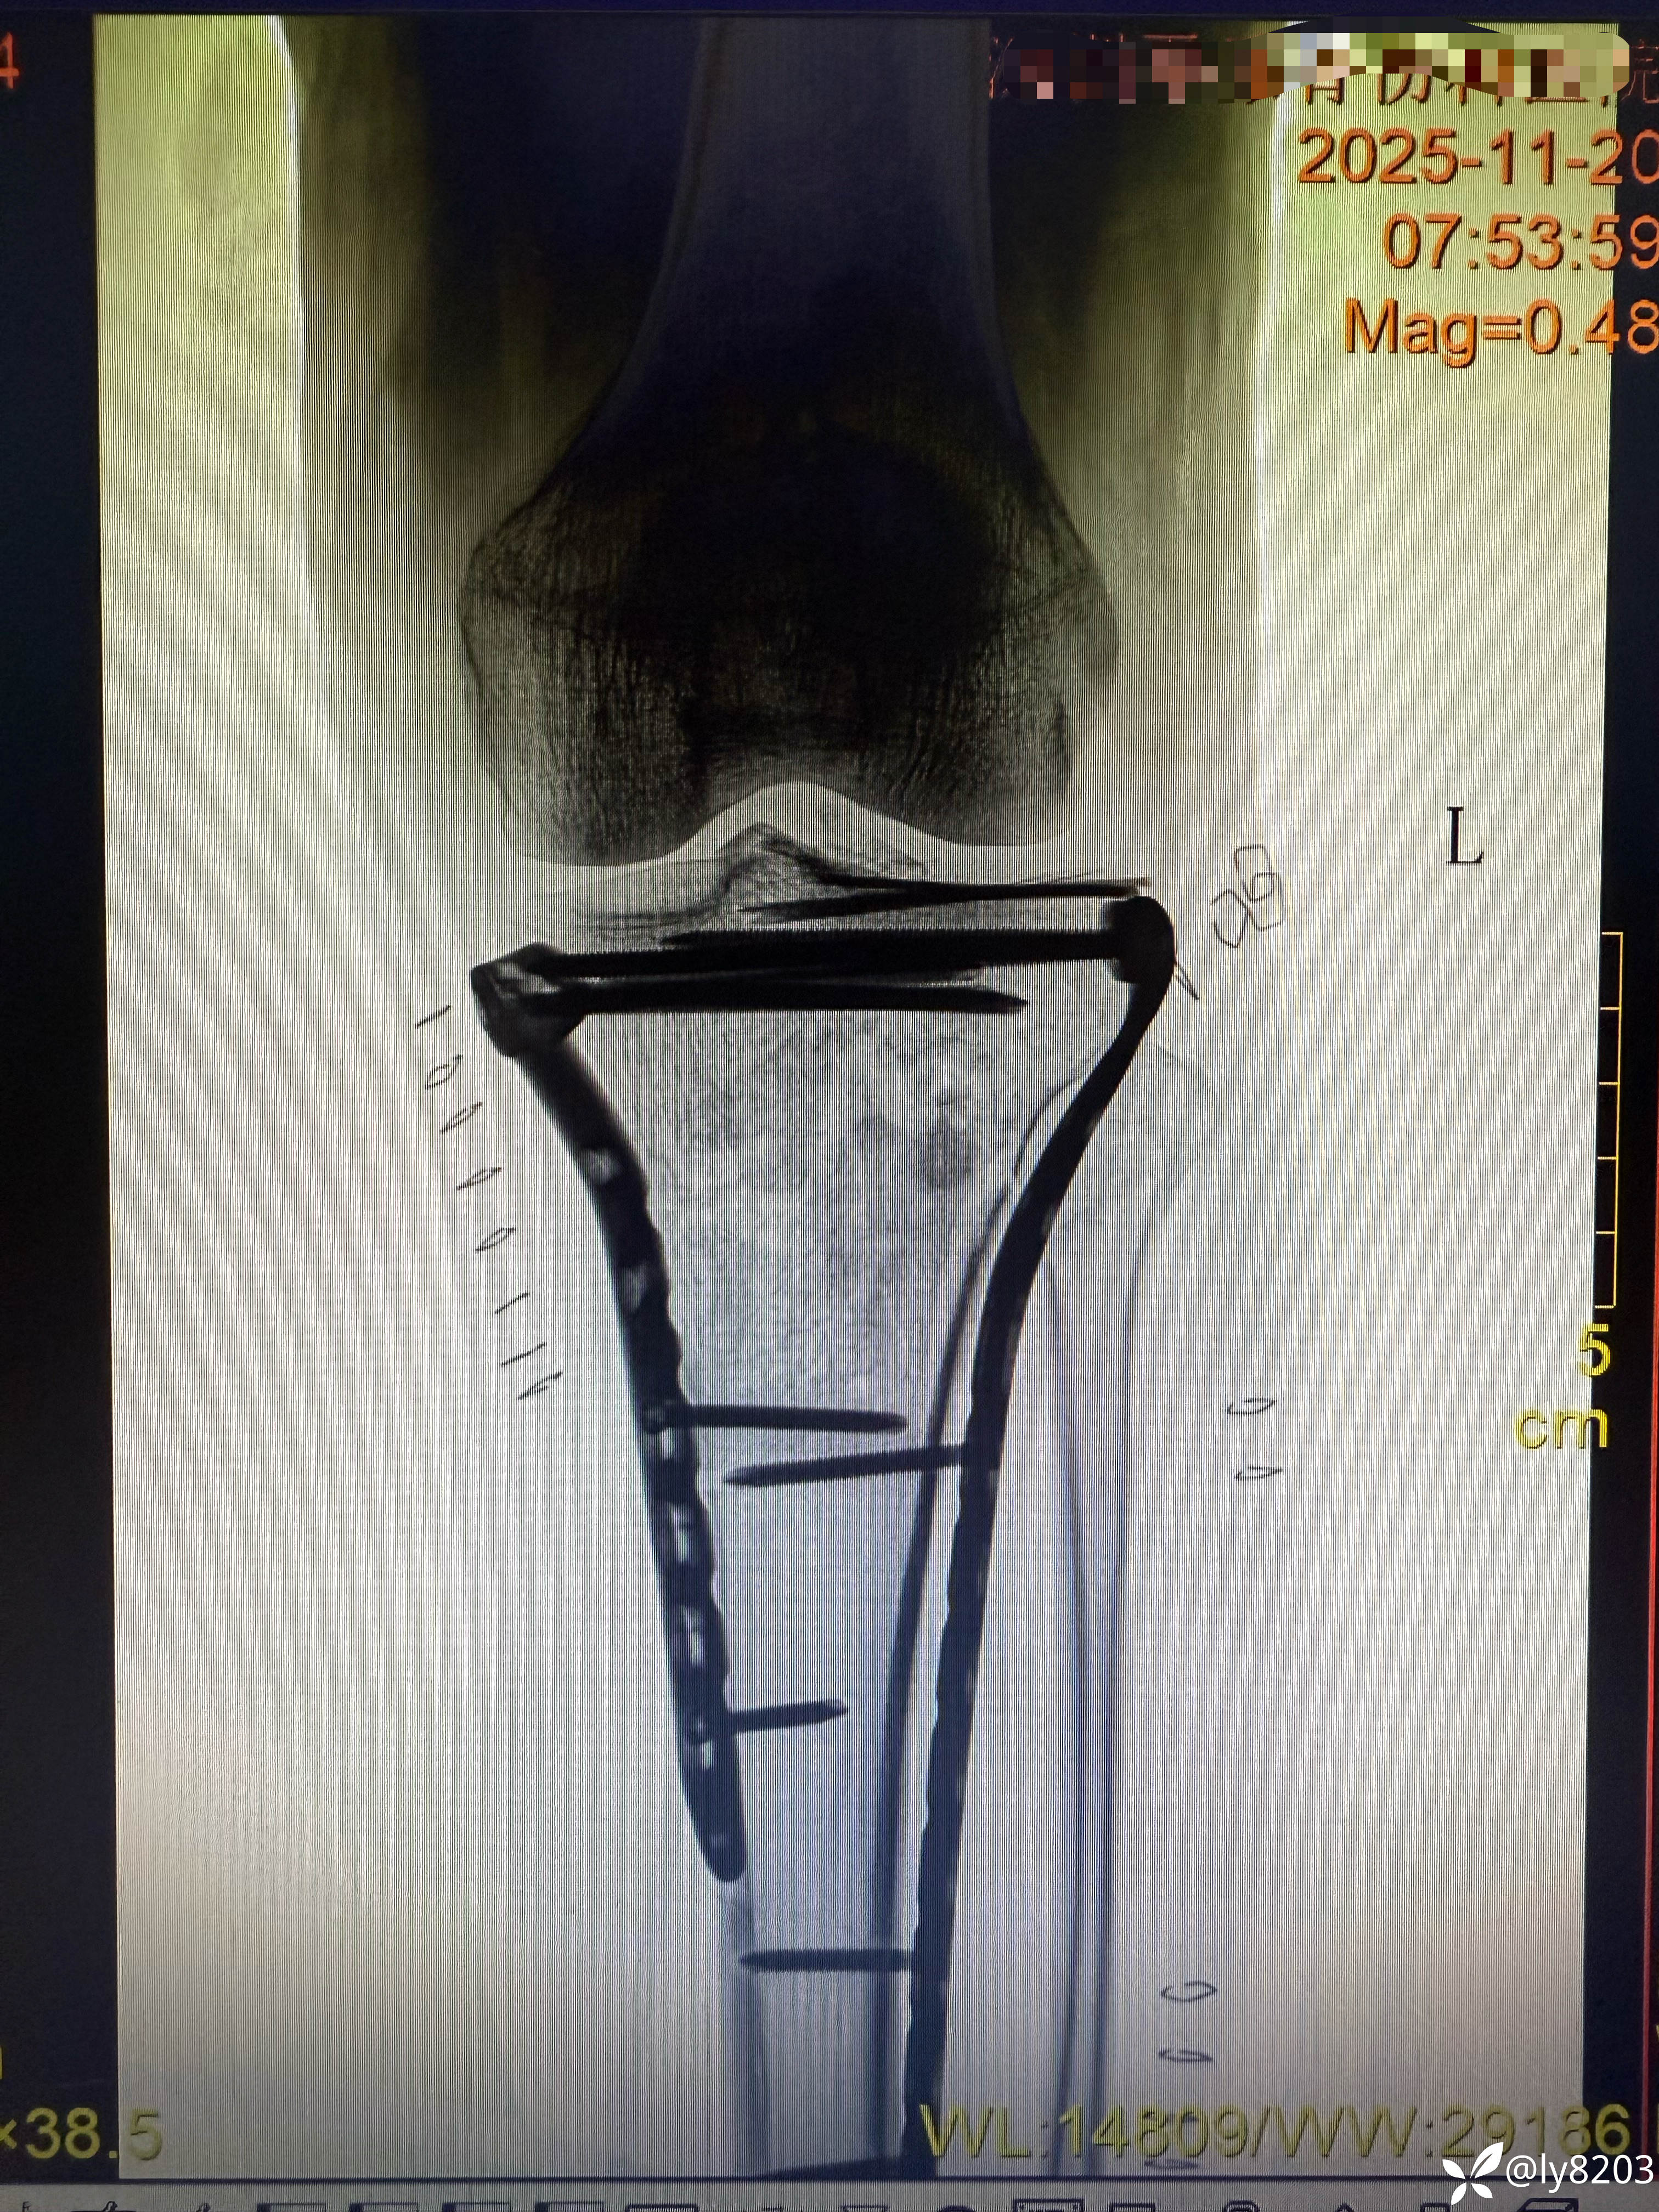

术后平片